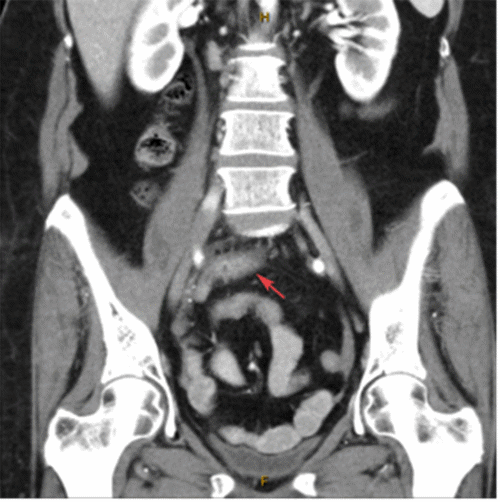

Figure 2. CT Axial Slices. Published with Permission

Images demonstrate normal proximal appendix thickening distally (2A, arrow) with associated distal fat stranding and fluid (2B, arrow).